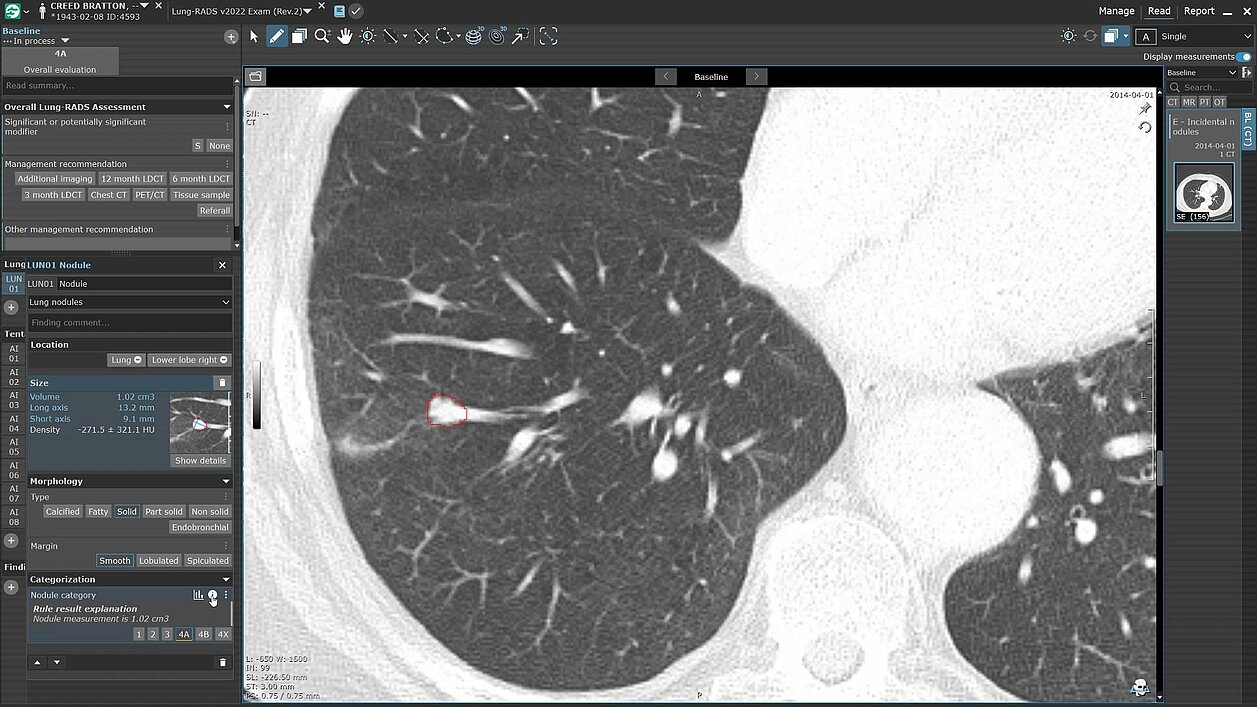

Discover the power of streamlined AI-driven lung screening with contextflow ADVANCE Chest CT integrated into mint Lesion. With automated lung nodule detection and segmentation, contextflow highlights findings directly within the mint Lesion platform, where users can seamlessly review, customize or add findings.

mint Lesion supports the Lung-RADS 2022 guidelines, featuring built-in automated scoring to enhance accuracy and consistency in lung nodule evaluation. contextflow ADVANCE Chest CT extends its capabilities beyond nodules, assisting in the analysis of COPD and *coming soon* identifying calcifications in coronary vessels, equipping users with deeper insights for comprehensive care.